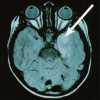

moderne Epilepsie-Diagnostik (3/3)

Bei Erkrankungen des Gehirns ändert sich in vielen Fällen das EEG. |

Weitere wichtige und sehr aussagekräftige apparative Untersuchungen in der Epilepsie- Diagnostik stellen die Computer-Tomographie (CT; Messung von Dichte-Unterschieden im organischen Gewebe mittels Röntgenstrahlen) und insbesondere die Magnet-Resonanz-Tomographie (MRT; Unter- suchung mit Hilfe starker Magnetfelder) dar. |